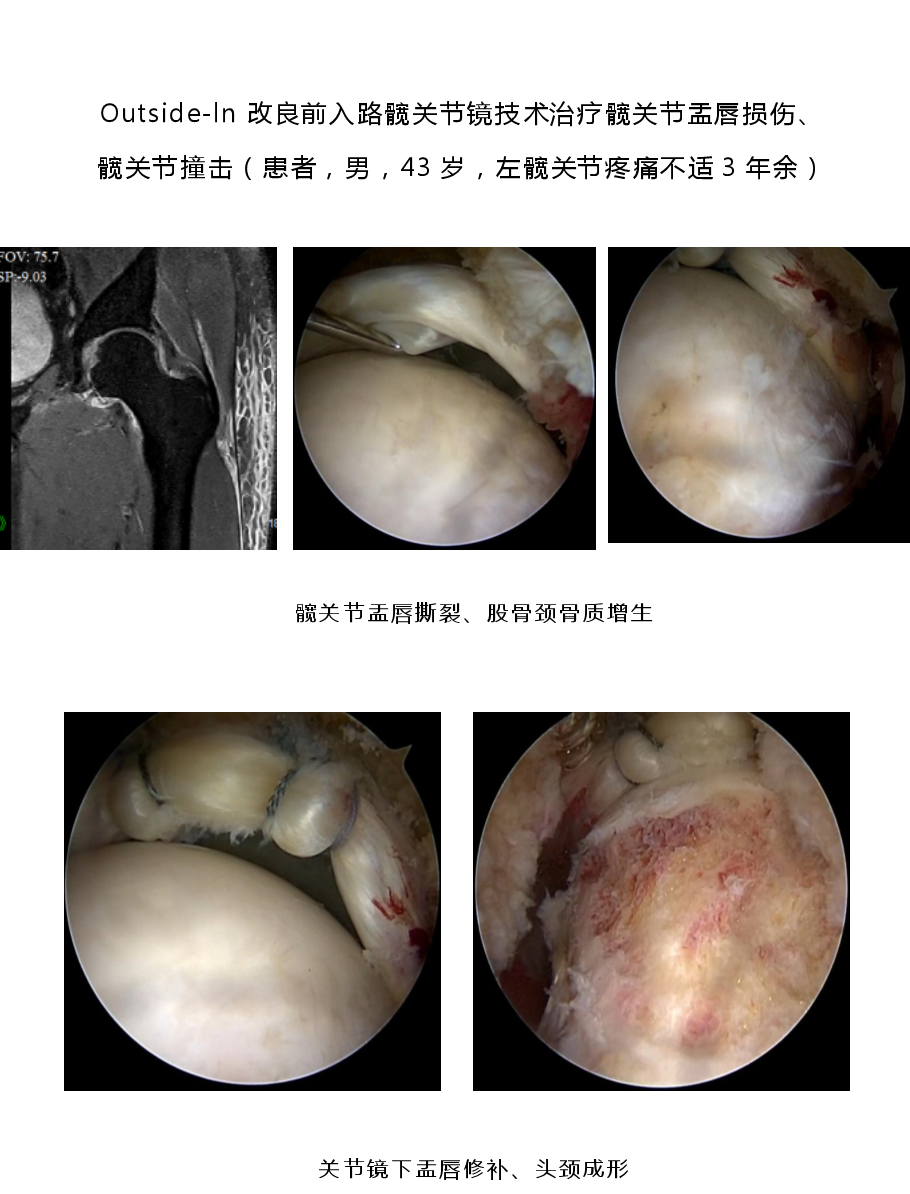

1.国际前沿的微创诊疗技术体系:科室聚焦肩、肘、髋、膝、踝多关节运动损伤,以 “精准化、个体化” 为核心,突破多项关键技术。膝关节领域:建立分龄化治疗方案 —— 青少年 “骨骺保护型前交叉韧带重建” 规避生长发育风险,成人 “联合前外侧韧带加强术” 提升术后稳定性,技术成熟度获行业广泛认可; 肩关节领域:个性化修复肩关节盂唇损伤、肩袖损伤,助力患者回归正常生活、重返运动;髋关节领域:为国内较早开展 “由外到内入路” 髋关节镜技术的科室之一,显著提升手术视野清晰度与操作安全性,年手术量超 300 台,居广东省前列。

3.核心业务范围:科室覆盖多关节运动损伤微创诊疗,主要包括:膝关节:前后交叉韧带重建、多韧带重建、半月板成形 / 修补 / 移植、髌股关节稳定术、关节软骨移植与修补、关节内游离体摘除;肩关节:肩袖撕裂关节镜下修补术、肩关节不稳关节镜下修复术(含 Laterjet 手术)、冻结肩关节镜下松解术、肩峰关节镜下减压成形术、SLAP 损伤修补术、肱二头肌腱固定术;髋关节:盂唇修补、股髋撞击症微创治疗、关节内游离体摘除;踝关节:踝关节不稳矫正、踝关节骨软骨损伤微创及开放治疗、跟腱腱病和断裂的微创及开放治疗、关节镜下各类踝关节疾病的微创治疗;肘关节:肘关节清理、网球肘、肘关节不稳、韧带重建;肘关节:腕关节清理、腕关节三角软骨损伤、腕关节不稳。